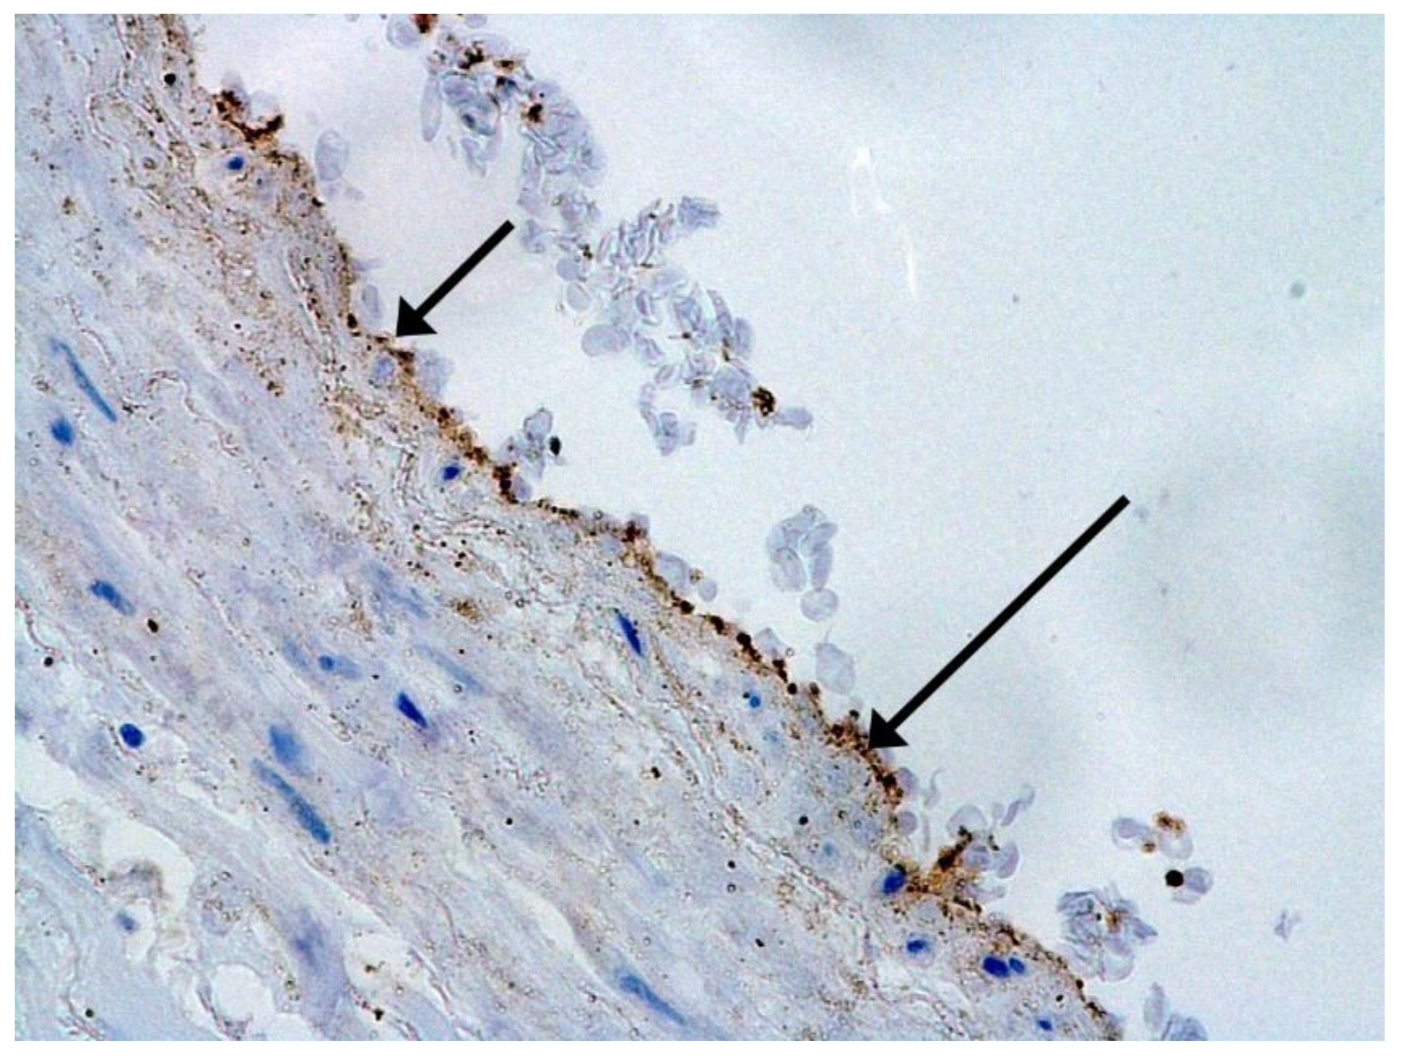

In many vessels, we also observe thrombi in different vessels (Figure 16 and Figure 17). We succeeded in detecting virus spike antigen in endothelial cells as well as in other layers of vascular walls. The formation of fibrin thrombi in blood vessels (probably DIC) and infiltration by T lymphocytes, including cytotoxic cells (Figure 18 and Figure 19), were seen not only in the parenchyma of the organs but in the surrounding tissues as well. It is important to compare the localization of virus antigens and cytotoxic CD8+ cells (Figure 20).

Figure 19. Infiltration of pericardium by CD8+ lymphocytes. IHC ×100.